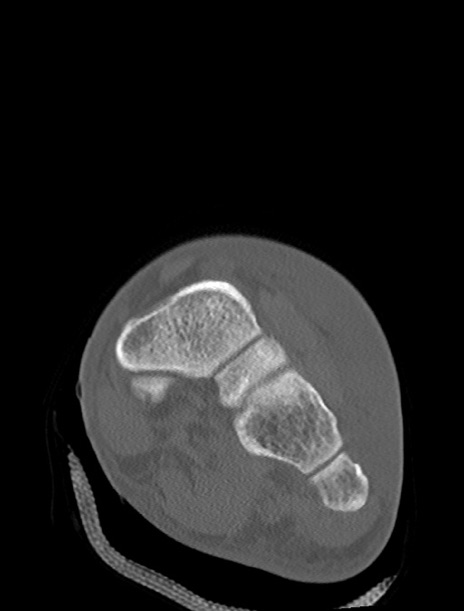

症例37 左足関節CT(冠状断像)

左足関節CT

3D再構成